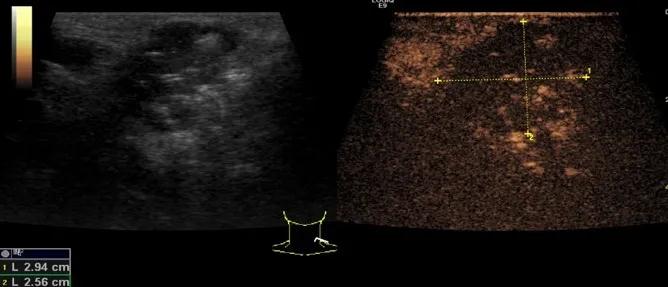

第二例是食管癌患者,术后半年余锁骨上固定淋巴结可触及肿大,疼痛非常明显,系统治疗后无缓解,患者希望通过局部处理缓解症状。造影显示强化信号明显,结节部分区域坏死,故主要针对强化区域从后向前的逐层的消融,皮下进行液体隔离减少烫伤。热消融后影像显示血流增强消失,弹性、硬度增高,一个月后复查显示充盈缺损,完全消融,疗效远超预期。

(病例2图例)